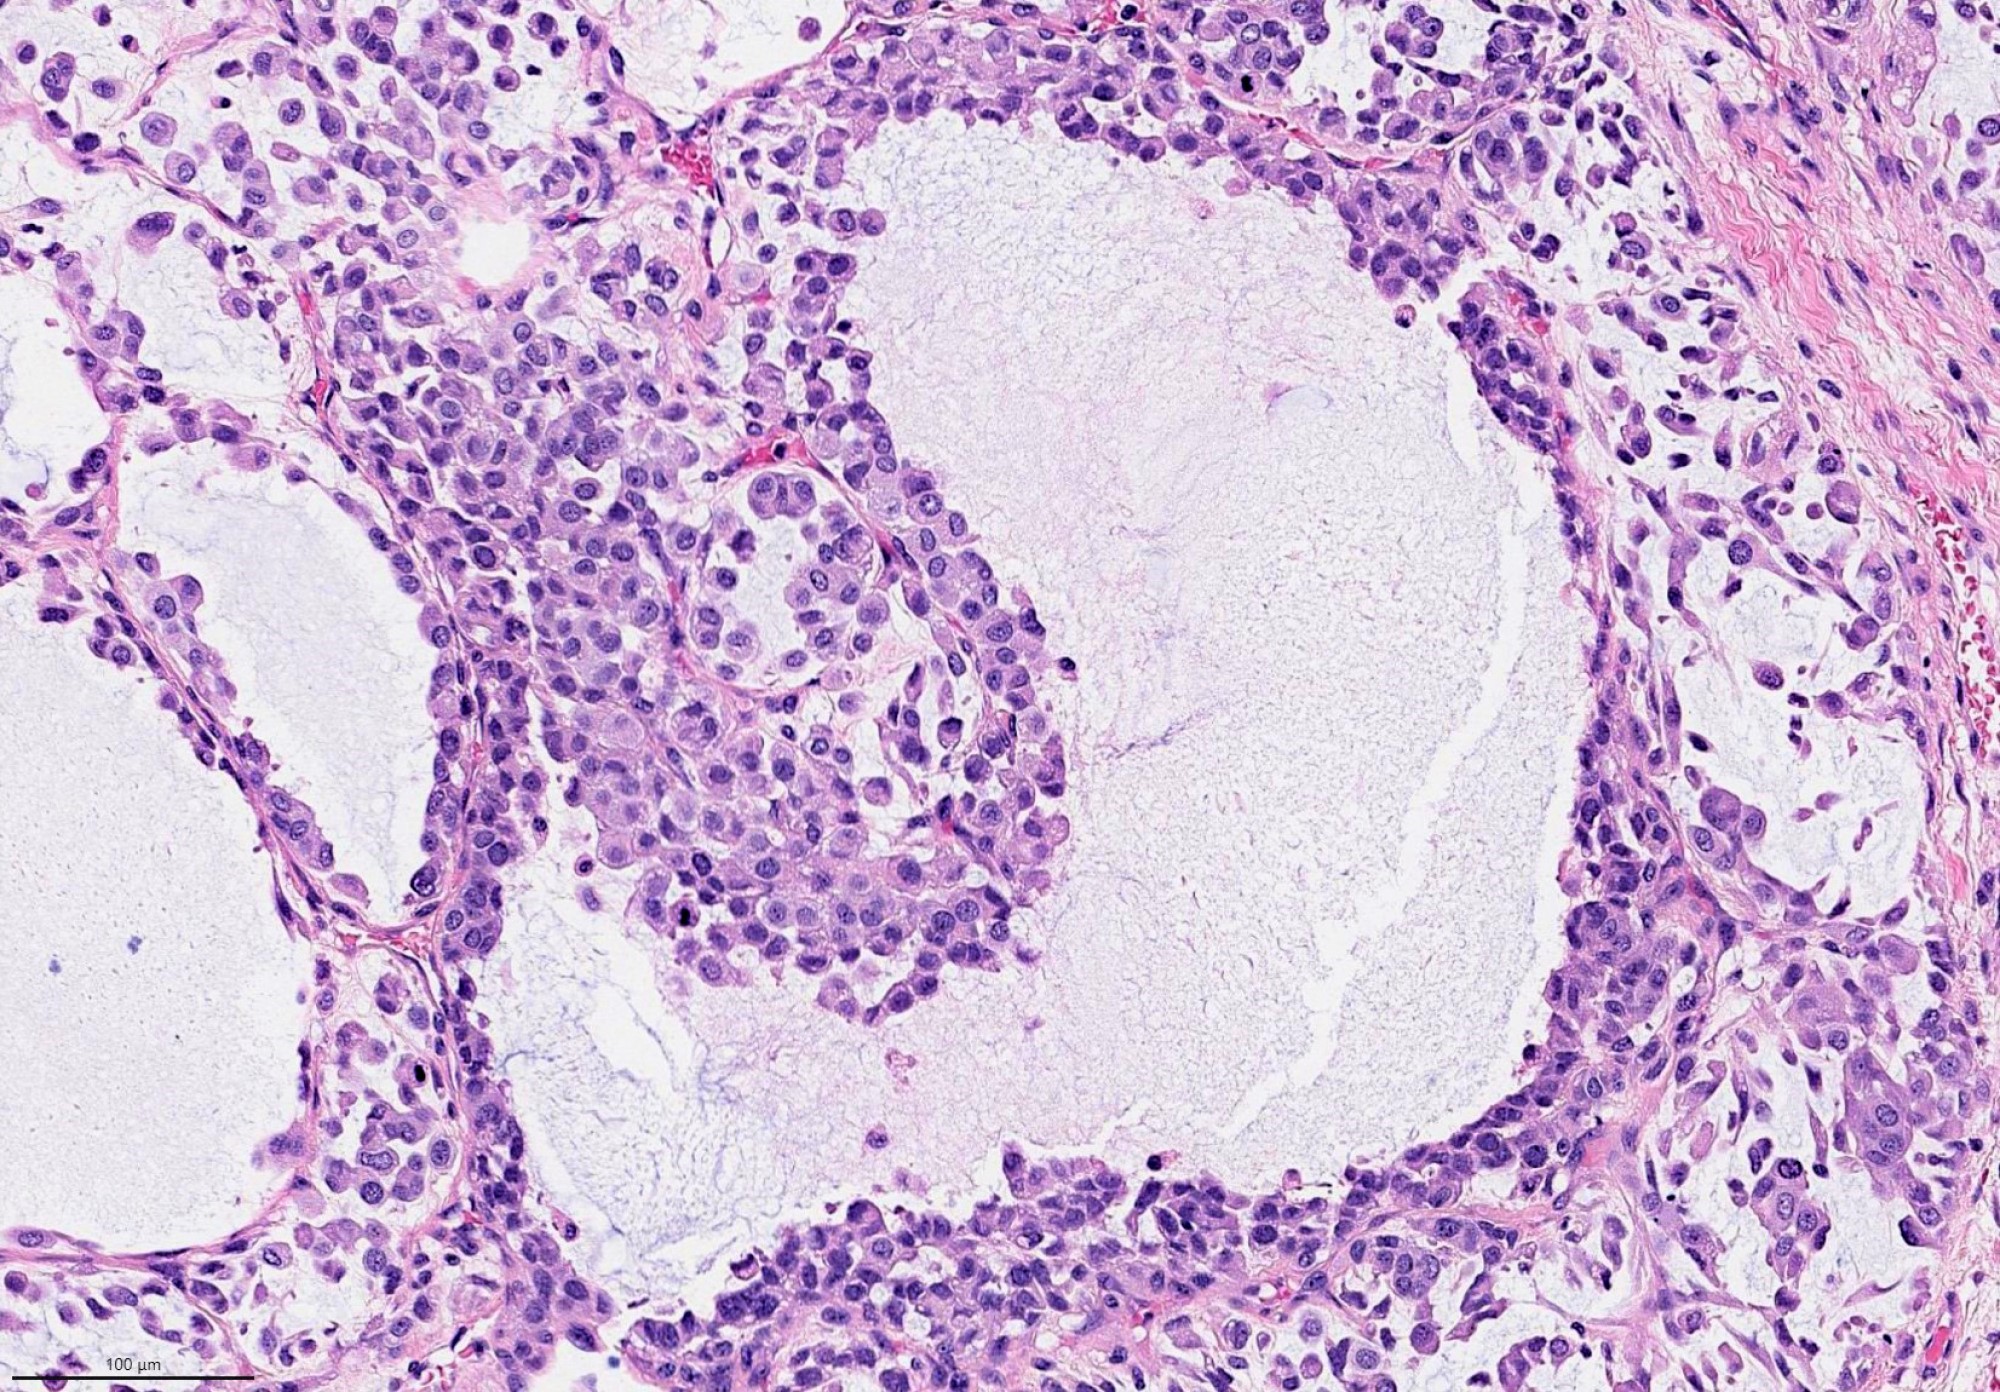

- Invasiveness is typically demonstrated as expansile invasive multinodular growth: myoepithelial carcinoma rarely shows infiltration of single cells / small clusters or desmoplastic reaction

- Nodules often have a hypocellular center with hyalinized stroma or bland necrosis surrounded by a hypercellular peripheral zone

- Tumor necrosis can be seen within the hypercellular central zone of a tumor nodule

- Currently, there is no well defined, widely accepted grading system: presence of tumor necrosis is considered by some as a feature of high grade myoepithelial carcinoma (Am J Surg Pathol 2015;39:931)

Contributed by Abeer Salama, M.D. and Bin Xu, M.D., Ph.D.